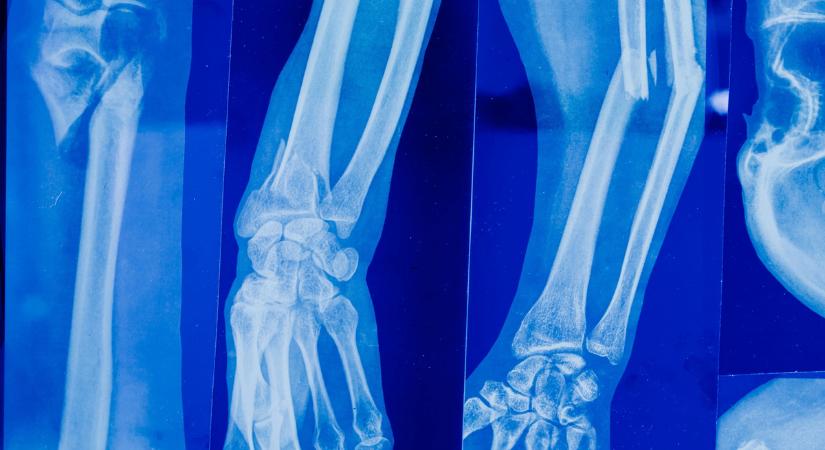

„27 évesen időskori betegséget diagnosztizáltak nálam"

Egy étrendi változtatás mentett meg az életét.